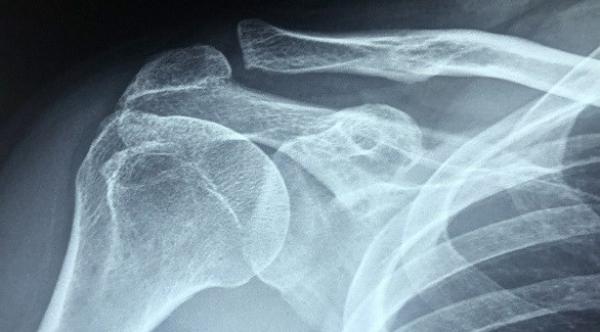

المصابون بهشاشة العظام أكثر عرضة لخطر حصوات الكلى